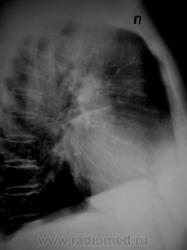

Снимки не увеличиваются, поэтому рискну предположить, что сердечные застойные дела?

Динамика через 7 дней после начатого лечения.

Интерстициальный отек легких сохраняется в меньшей степени, но обозначился междолевой плеврит справа.

Центральный венозный застой, м\д плеврит справа.

Пневмонии не вижу. Легочная гипертензия. Наложение мягких тканей грудной клетки на нижнее легочное поле справа. Если есть клиника - лечить ОРВИ и к кардиологу, УЗИ сердца.

У междолево плеврита справа два пути :либо нарастание и прорыв в пл. полость-либо рассасывание и организация.Как бодут лечить. А причина его возникновения может быть ТЭЛА-тогда жди рецидива в другом месте.